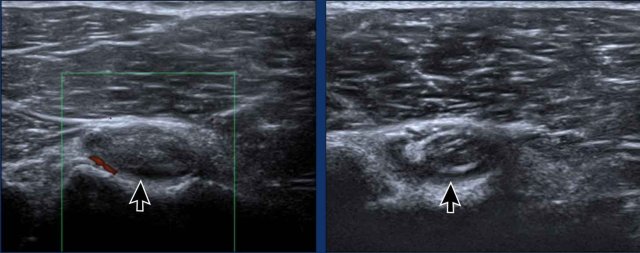

Image during exoratation (left) and endorotation (right) Image during exoratation (left) and endorotation (right)

Impingement

During endorotation a normal subscapular tendon should show almost complete passage underneath the coracoid process.

Impingement is suspected when a residual portion of the tendon is still visible during maximum endorotation.

Images

During endorotation there is incomplete passage under the coracoid and buckling of the subscapular tendon.